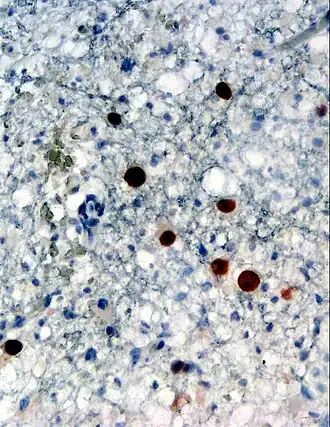

JCV kan door de bloed-hersenbarrière het centrale zenuwstelsel bereiken waar het de oligodendrocyten en de astrocyten infecteert, mogelijk door de 5-HT2A-serotonine-receptor/[6] Ook bij symptoomloze mensen kan het JC virus in de hersenen worden teruggevonden.[7]

Indien door immuundeficiëntie of immunosuppressie het JCV geheractiveerd wordt, valt het de eerder geïnfecteerde weefsels aan. In de nieren resulteert dit in hemorragische cystitis en uretrale stenose; in de hersenen veroorzaakt het gewoonlijk fatale progressieve multifocale leukencefalopathie door het vernietigen van de oligodendrocyten. Verschillende studies sinds anno 2000 vermoeden eveneens een link tussen het virus en colorectale kanker, aangezien JCV werd teruggevonden in kwaadaardige darmtumoren. Doch deze bevindingen zijn nog steeds controversieel.[8]